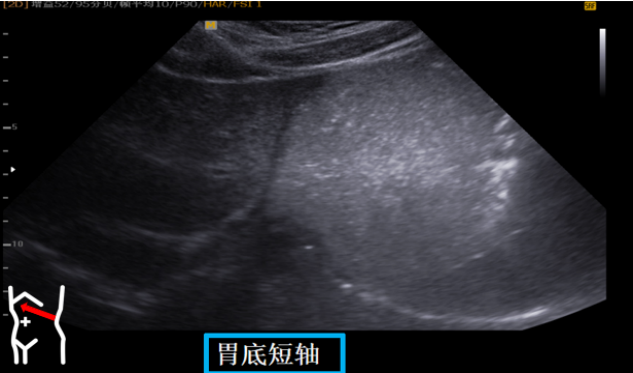

第二组胃底切面

受检者右卧位我们降探头置放左肋下朝左侧上翘以脾下缘作为寻找胃底短轴界面。